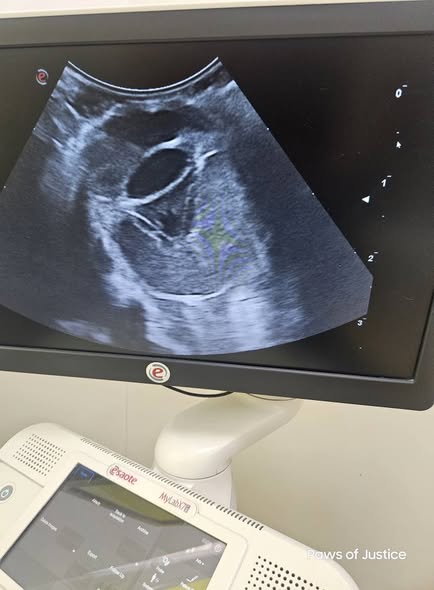

We did an ultrasound on the other eye, the lens is obscured and he can't see, but at least the eye can remain.